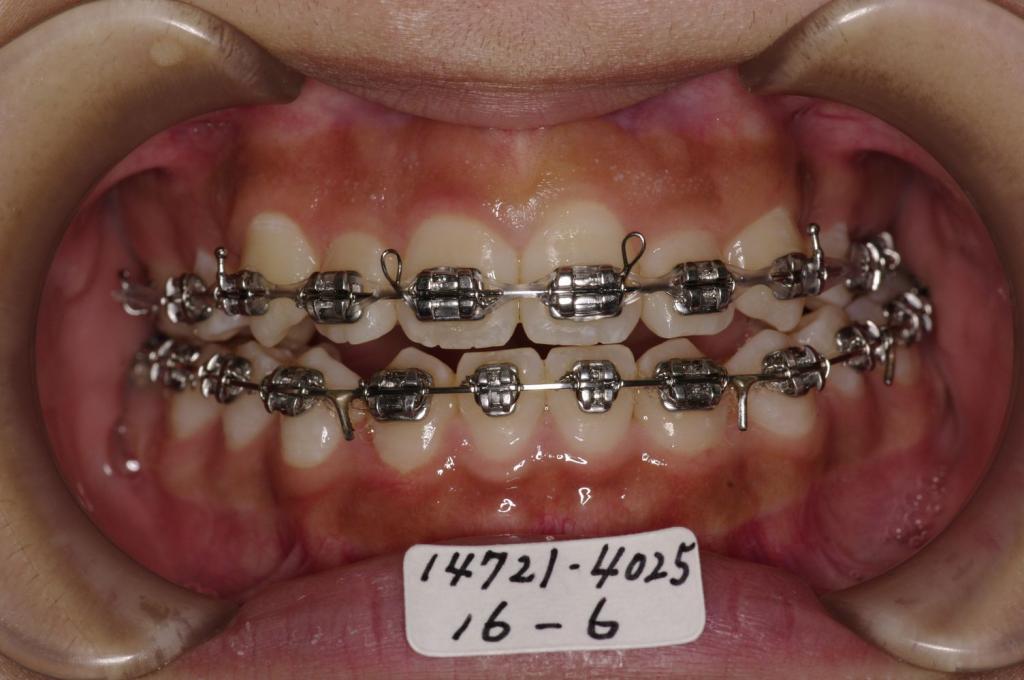

装置の種類及び治療法 診断:下顎両側側切歯先天欠如 叢生 開咬

治療方法および装置:マルチブラケット装置

High pull J-hook headgear

抜歯:右上4 /左上4

右下 /左下

欠損歯:右上 /左上

右下2 /左下2

治療前

歯欠損の矯正治療前口内写真NO.148